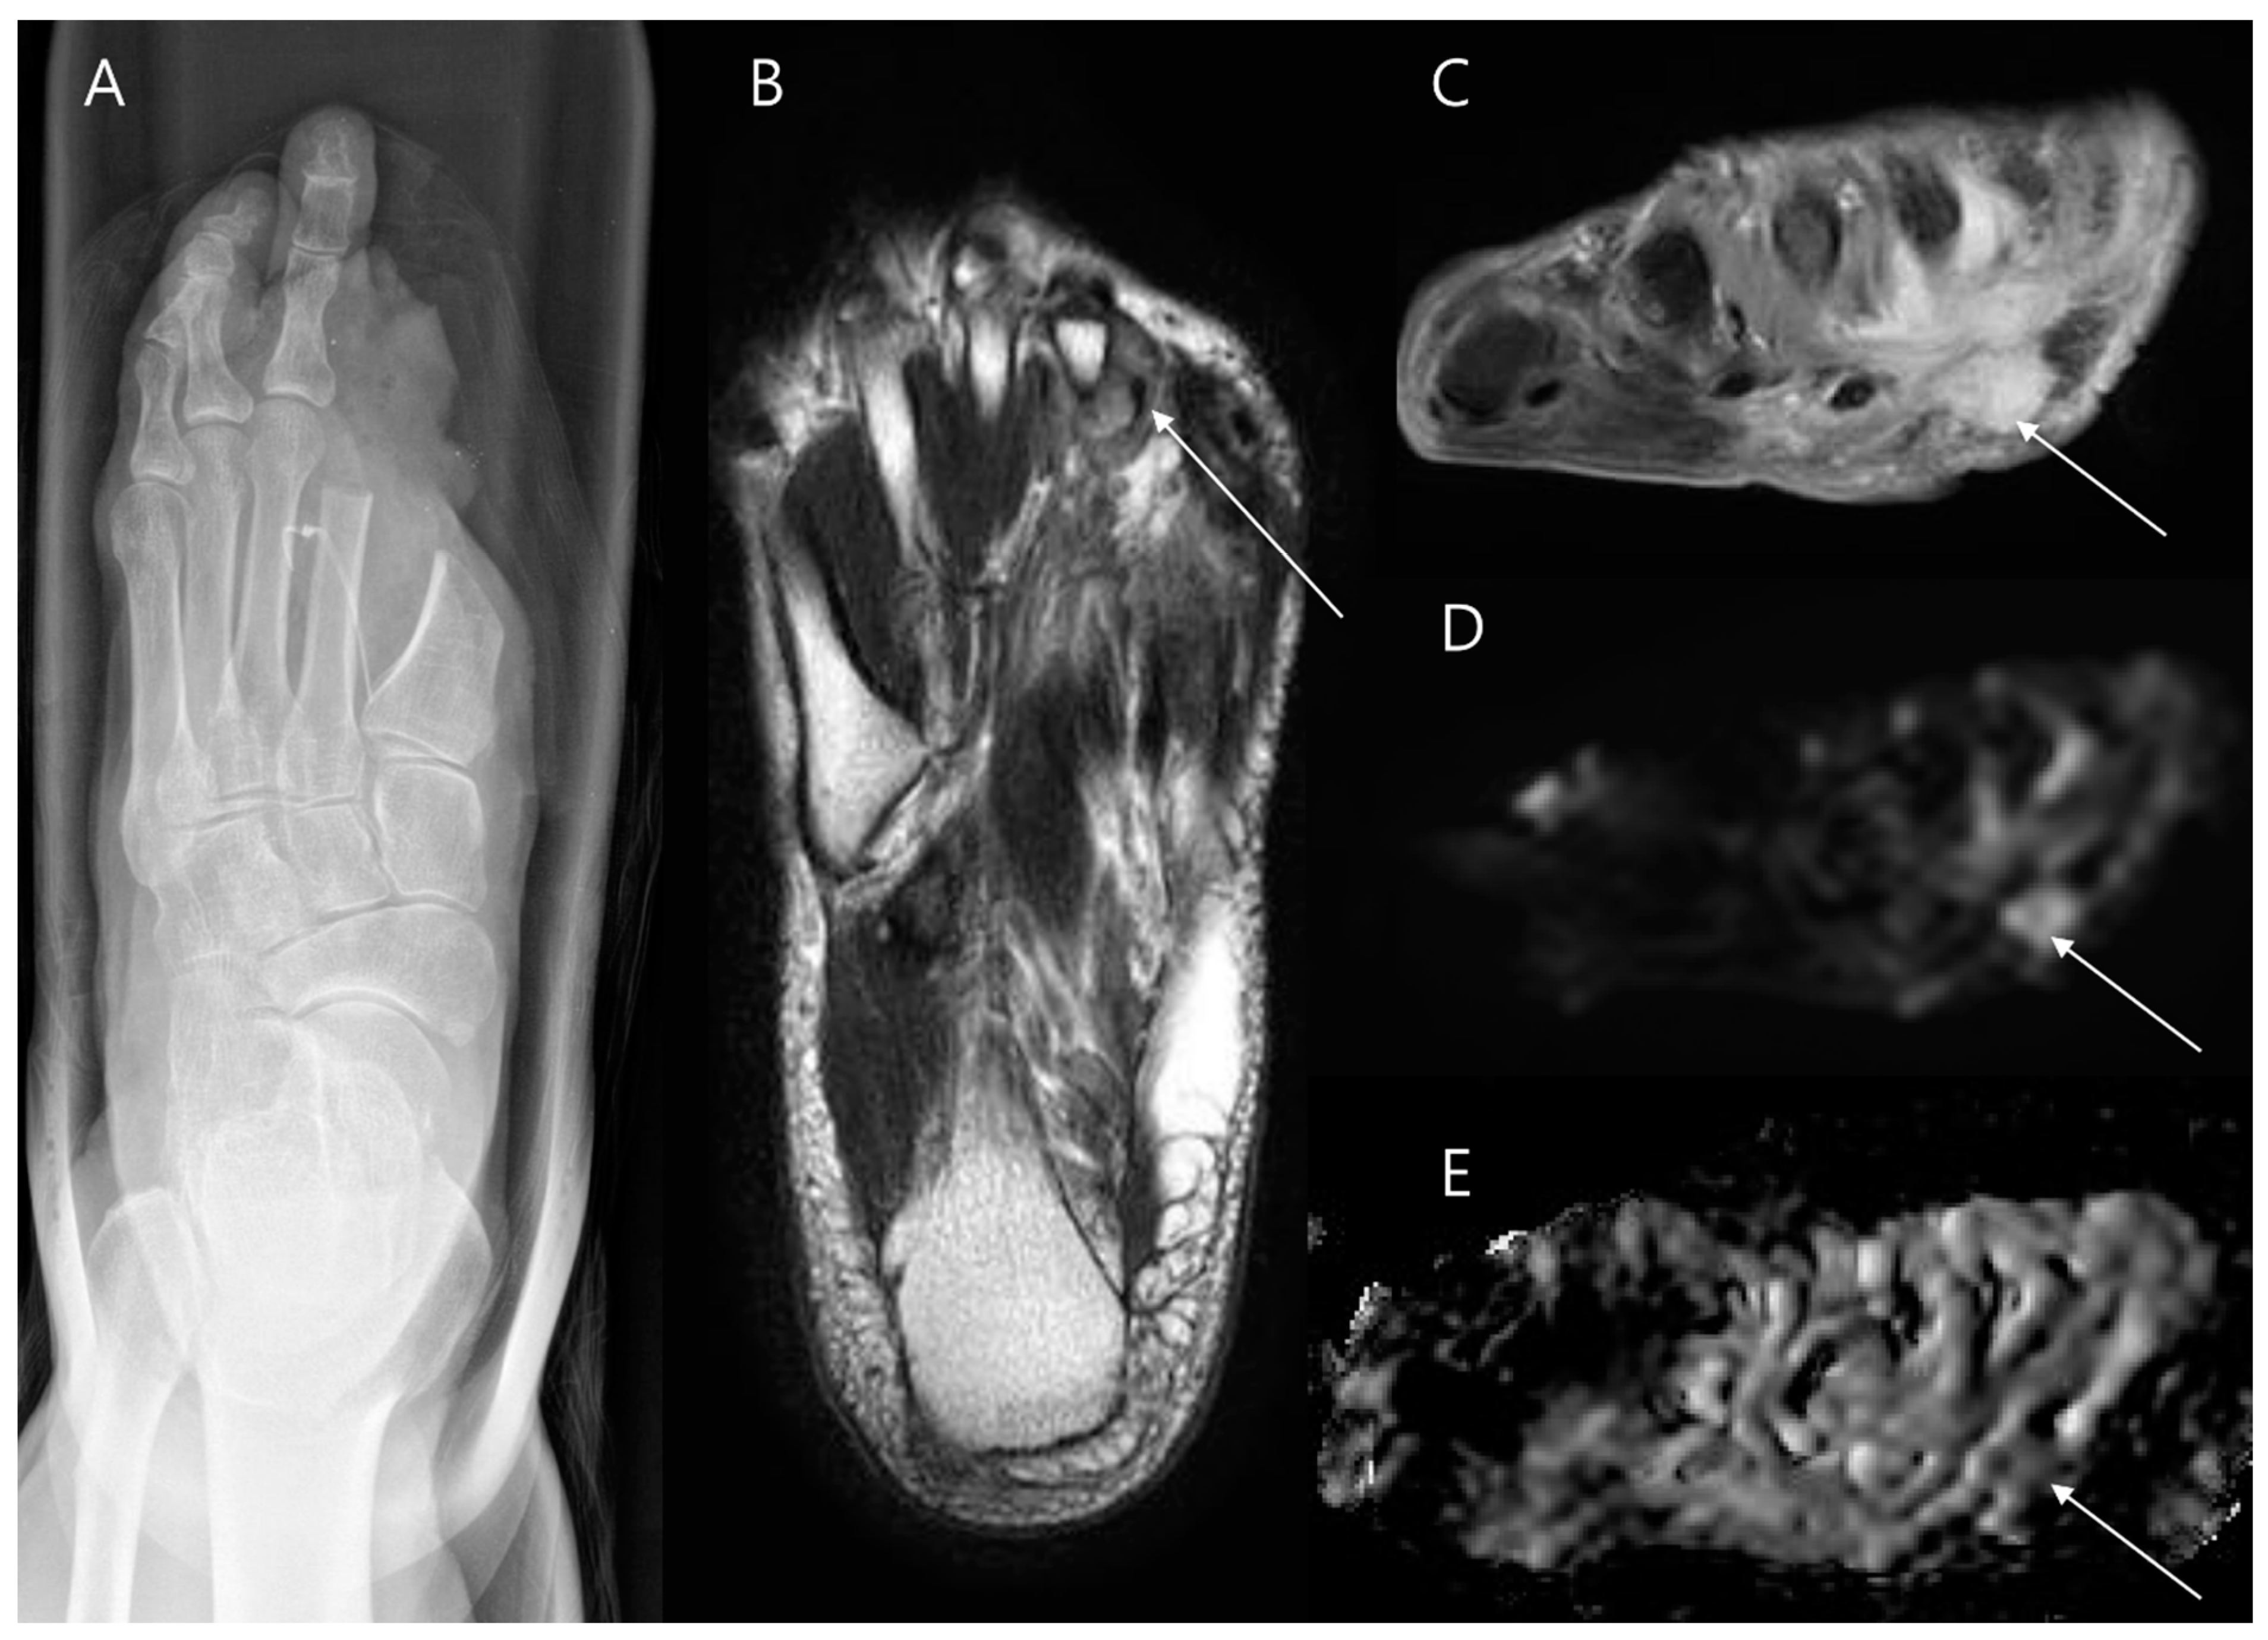

- Noebauer-Huhmann, I.M.; Grieser, T.; Panotopoulos, J.; Dieckmann, K.; Lalam, R.K.; Bloem, J.L.; Weber, M.A. Presurgical Perspective and Posttreatment Evaluation of Soft Tissue Tumors of the Ankle and Foot in Adults. Semin. Musculoskelet. Radiol. 2022, 26, 730–743. [Google Scholar] [CrossRef]